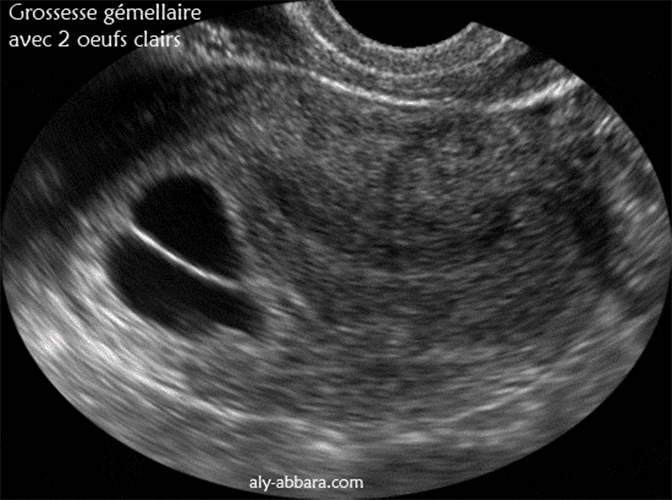

Une coupe échographique transversale d'un utérus gravide, on observe la présence de

deux sacs gestationnels intra-utérins de 26 et 22 mm de grands axes, sans aucune

structure

embryonnaire identifiable. Il s'agit de double ufs clairs